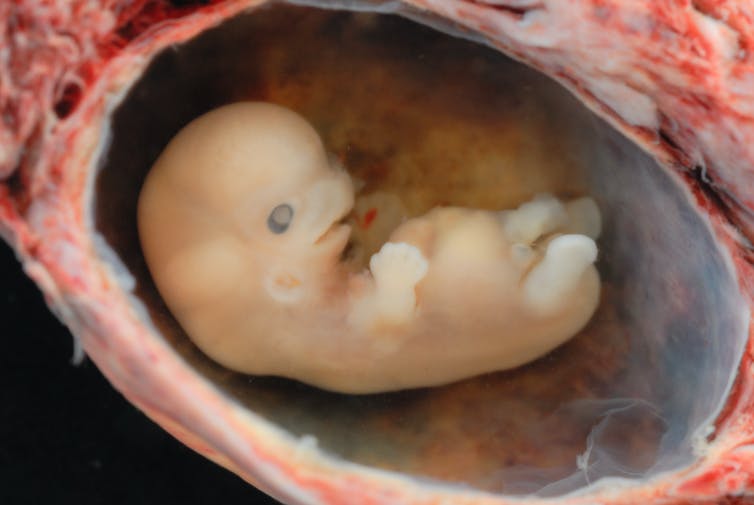

스워스모어 대학(Swarthmore College)의 하워드 A. 슈나이더만 생물학(Howard A. Schneiderman Professor of Biology) 명예 교수인 스콧 길버트(Scott Gilbert)는 발달 생물학 표준 교과서의 저자이다. 그는 생물학적 관점에서 볼 때 모두 인간 생명의 시작점이 될 수 있는 다섯 가지나 되는 발달 단계를 확인했다. 현재 과학이 알고 있는 생물학은 이러한 단계를 구분할 수 있지만 이 단계 중 어느 단계에서 생명이 시작되는지는 결정할 수 없다.

이 단계의 첫 번째 단계는 수정란이 완전한 인간 유전 물질로 형성될 때 난관에서 수정되는 것이다. 그러나 모든 사람의 몸에 있는 거의 모든 세포는 그 사람의 완전한 DNA 서열을 가지고 있다. 만약 유전 물질만으로도 잠재적인 인간이 될 수 있다면, 우리가 항상 그렇듯이 피부 세포를 흘리는 순간 우리는 잠재적인 인간을 잘라내고 있는 것이다.

두 번째 그럴듯한 단계는 수정 후 약 2주에 발생하는 장배 형성(gasstrulation)**이라고 한다. 그 시점에서 배아는 일란성쌍둥이 또는 세 쌍둥이 또는 그 이상을 형성하는 능력을 잃는다. 따라서 배아는 생물학적 개체가 되지만 반드시 인간 개체는 아니다.

세 번째 가능한 단계는 태아의 뇌에서 인간 특유의 뇌파 패턴이 나타나는 임신 24~27주이다. 이 패턴이 사라지는 것은 인간 사망에 대한 법적 기준의 일부이다. 대칭적으로 말하면, 아마도 그 모습은 인간 생명의 시작을 표시하는 것으로 간주될 수 있다.

네 번째 가능한 단계는 미국에서 낙태를 합법화한 로 대 웨이드(Roe v. Wade) 판결에서 인정된 것으로, 태아가 일반적으로 이용 가능한 의료 기술의 도움으로 자궁 밖에서 생존할 수 있게 되는 생존 가능성이다. 오늘날 우리가 가진 기술로 그 단계는 약 24주이다.

마지막 가능성은 탄생 그 자체이다.